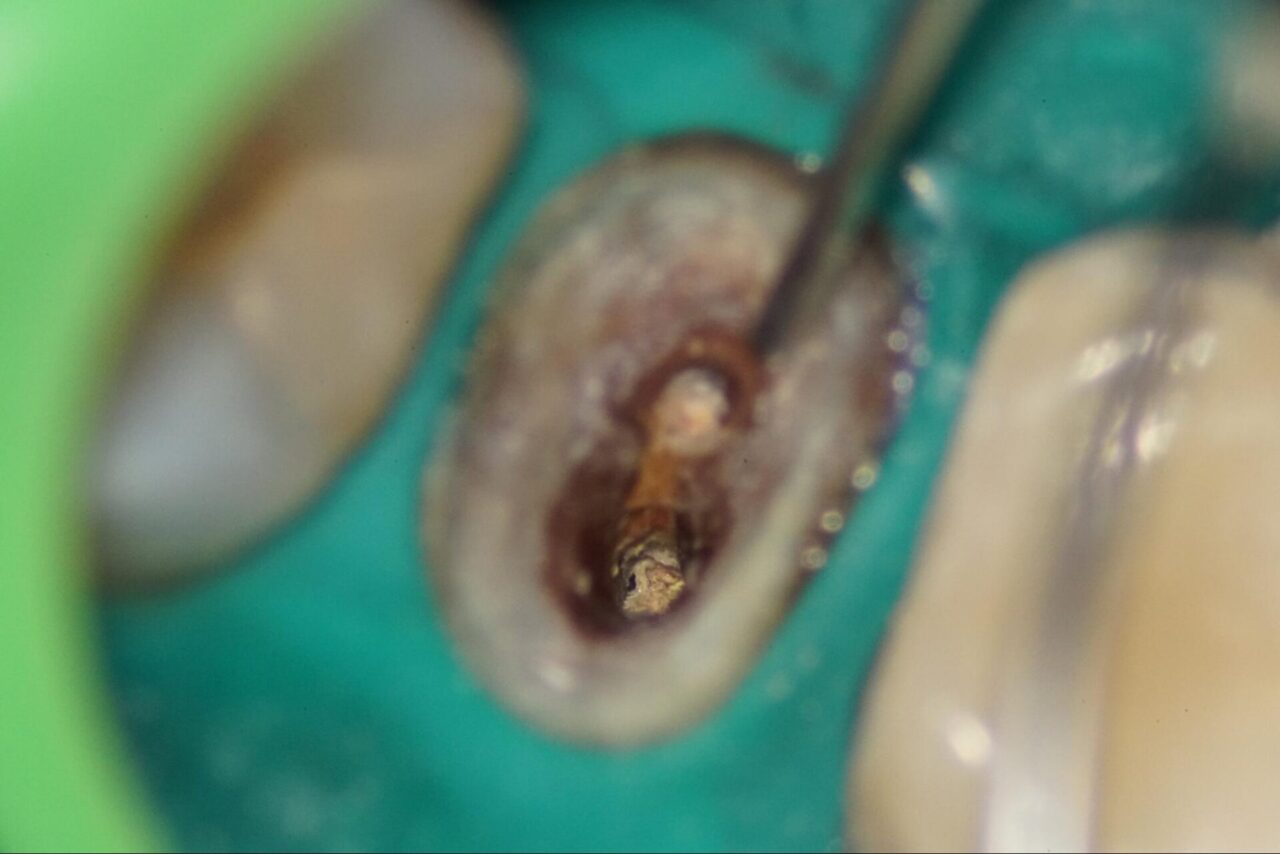

冠を外した後にファイバーポストが入っているので、それを慎重に削って行きます。

少しずつ根管内壁が視えて来ました。

頬側根は根管が視えて来ました。よく診ると根管内壁と以前のファイバーポストの境が変色している事が確認できます。感染がそこに存在する事です。

頬側の根管内の充填物を慎重に除去して行きます。